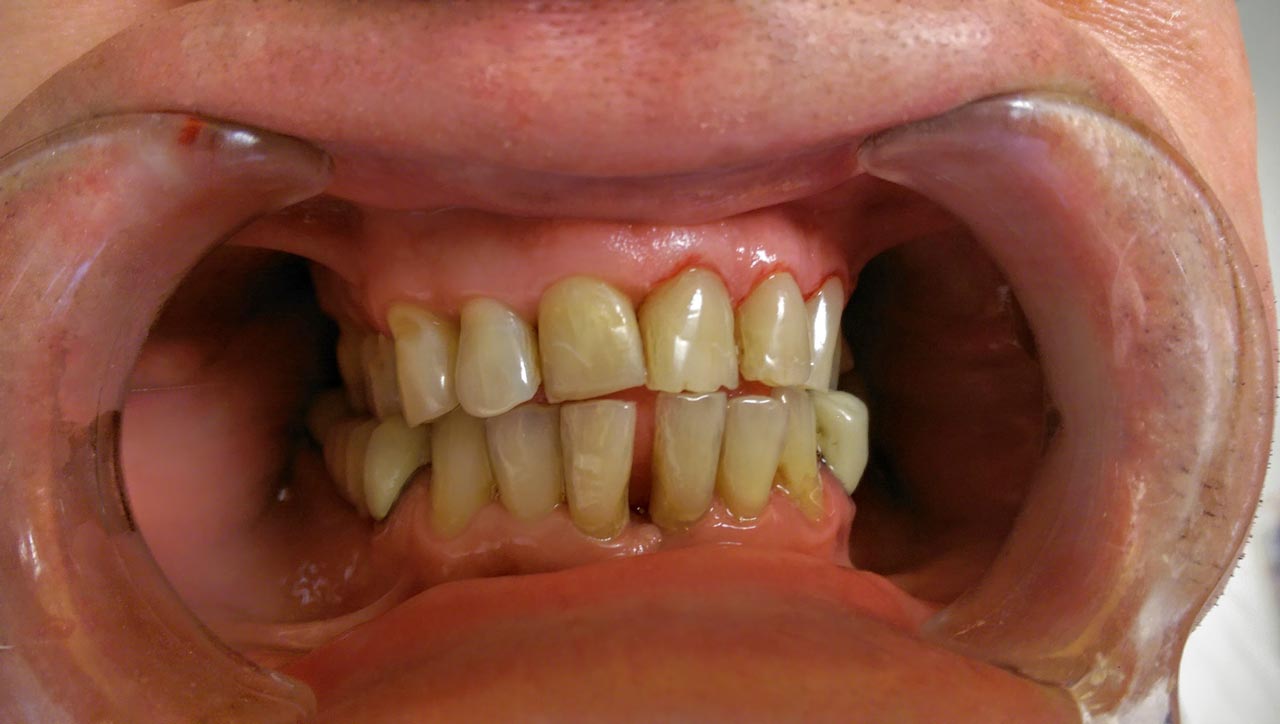

Alsó állcsont teljes rehabilitációja 72 óra alatt

Alsó állcsont teljes rehabilitációja 72 óra alatt, azonnal terhelhető implantátumokkal súlyos paradontitisben szenvedő dohányzó páciens esetében. Az alsó állcsont fogai mind mozogtak az előrehaladott fogágypusztulás miatt.

A fogakat eltávolítottuk, a gyulladt, fertőzött csontot kitakarítottuk, kifertőtlenítettük, majd azonnal implantáltunk.

Svájci, IHDE márkájú, azonnal terhelhető implantátumokat helyzetünk be, és ezekre harmadnapra rögzített, hosszútávú, fémvázas, esztétikus műanyaggal leplezett hidat ragasztottunk be.

Ezt az ideiglenes hidat a sebek gyógyulása miatt használjuk, de tartóssága miatt véglegesként is használható. A legtöbb esetben, ahogy itt is, 6 hónap múlva porcelán hídra cseréljük, a teljes gyógyulás után.